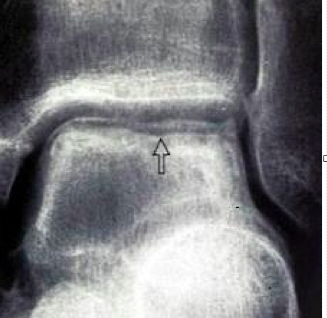

What is Hawkin’s sign

A

• subchondarl lucency in the talar dome best seen on AP

• 6-8 weeks

• evidence that there is vascularity, good sign

• Bad sign if you get relative sclerosis

How well did you know this?

What are complications associated with talar neck fractures?

• Osteonecrosis

• hawkins sign

• subchondral lucency best seen on mortise Xray at 6-8 weeks

• indicates intact vascularity with resorption of subchondral bone